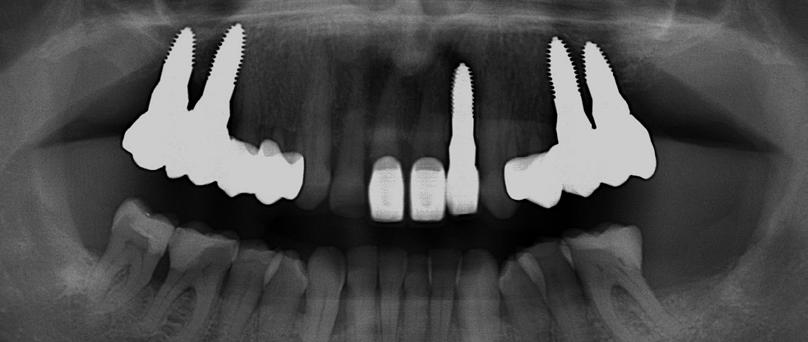

Egy fiatal páciens jelentkezett nálunk, akinek eltörött a szabad véggel rendelkező hídja (1. ábra). A hiányzó, első premoláris fog esetén implantációs pótlást javasoltunk. A csontállomány értékeléséhez CBCT-vizsgálatot végeztünk, és az elemzéséhez NNT Viewert (NewTom) használtunk, és copaSKY 4×10 mm-es (bredent medical) implantátumot választottuk a fog pótlásához

1. ábra: Műtét előtti fogászati panorámafelvétel, amelyen a hiányzó felső állcsont jobb első premolárisát és a szabad véggel rendelkező hidat láthatjuk. — 2. ábra: Az implantátum méreteinek megtervezése CBCT-vel. 3. ábra: Bukkális lágyrészdefektus. — 4. ábra: A biológiai szélesség értékelése a vertikális lágyszövetvastagság alapján. 5. ábra: Palatinális „tekercslebeny” – Palatal roll flap. — 6. ábra: Bredent medical copaSKY 4x10 implantátumbeültetés. 7. ábra: Szubkresztális implantátumbeültetés a várható biológiai szélességnek megfelelően.

(2. ábra). A lágyszövetek értékelése Seibert szerinti I. osztályú csontdefektust állapított meg (3. ábra), ezért a beavatkozáskor palatinális „tekercslebenyt” preparáltunk (palatal roll flap), és implantációt végeztünk, hogy kompenzálni tudjuk a bukkális lágyszövet-behúzódást. Megmértük a vertikális lágyszövetvastagságot, és úgy terveztük, hogy a szubkresztális implantátum beültetése összhangban legyen a biológiai szélesség kialakulásával a transzgingivális gyógyulási periódus alatt (4. ábra)